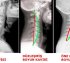

Boyun düzleşmesi, servikal omurganın (boyun bölgesi) doğal olan C şeklindeki eğrisinin azalması veya tamamen kaybolmasıyla ortaya çıkan bir duruştur. Normal şartlarda omurga kıvrımları vücut yükünü dengeler, kaslara ve eklemlere minimum yük bindirir. Ancak boyun eğrisinin düzleşmesi, hem kas-iskelet sistemini hem de sinirsel yapıları etkileyebilir.

Servikal omurga doğal olarak boynun hafif öne doğru kavis yapan eğrisine sahiptir. Bu eğri yalnızca estetik değil; biyomekanik açıdan da kritik öneme sahiptir.